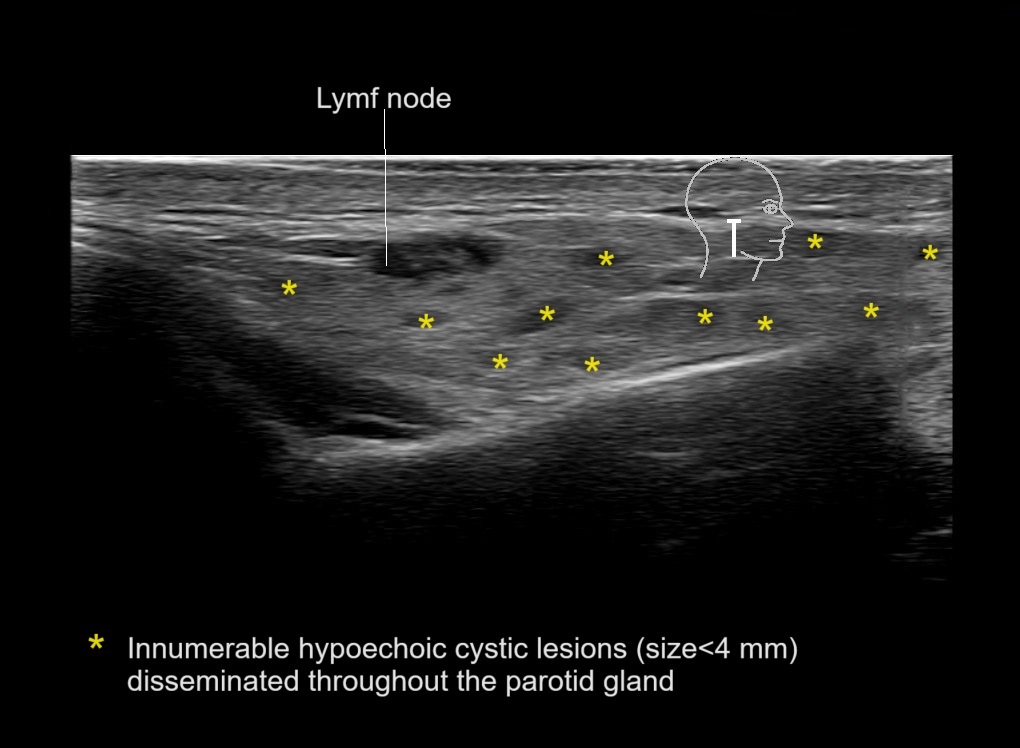

With ultrasound signs of inflammation can be visualized. Edema can be seen as a hyperechoic appearance of the subcutaneous fat, sometimes separated by hypoechoic fluid filled area’s, known as cobblestone appearance. Increased vascularization (hypervascularity) can be seen on colour Doppler. An abscess will appear as a fluid collection appearing as an irregular hypoechoic area with heterogeneous internal echoes and a thickened wall. Posterior acoustic enhancement can be present, and there is vascularity around but not within the mass. Under ultrasound guidance, abscesses can be managed by needle aspirations (18G) under antibiotic cover.

Study the first image to recognize the different layers. If you are sure about the layers, swipe to the second image to view the answer (if applicable).

Hover over an image to view the secondary image or click on the image title for more information.